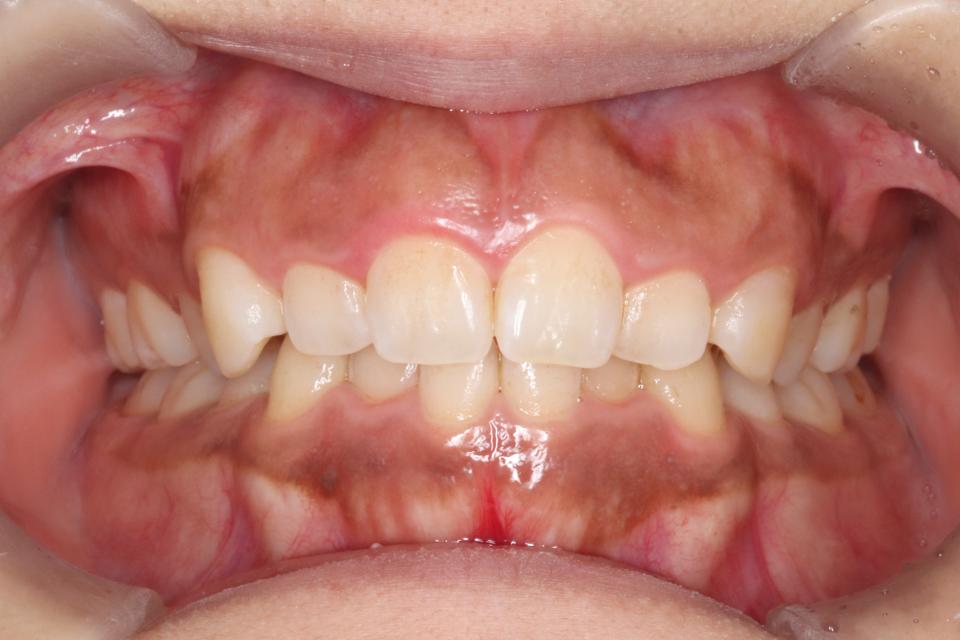

矯正治療前

30代女性の患者さんです。

前歯の歯並びが気になり来院されました。

マウスピース型の矯正治療装置を使用し、前歯の歯並びのみの改善を行いました。